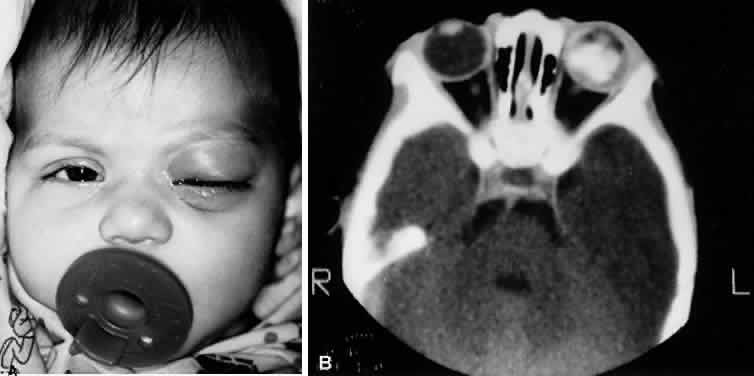

H. influenzae type B cellulitis typically begins with mild upper respiratory tract infection, fever, leukocytosis, and unilateral hyperemia and edema of the soft tissues of the eyelids. A sharply demarcated, purple discoloration of the skin of the eyelids and adnexal region is characteristic (Fig. 12). Mild conjunctival hyperemia and chemosis may be present.

Fig. 12. A. Two-year-old African-American girl with preseptal cellulitis due to type b H. influenzae. B. Seven-year-old white boy with preseptal cellulitis due to S. pneumoniae.

Fig. 22. Inflammatory proptosis originally diagnosed as orbital cellulitis (A), but later diagnosed as necrotic retinoblastoma (B).

Fig. 23. Inflammatory proptosis originally diagnosed as orbital cellulitis, but later diagnosed as rhabdomyosarcoma. Figure depicts patient's status after biopsy through brow.